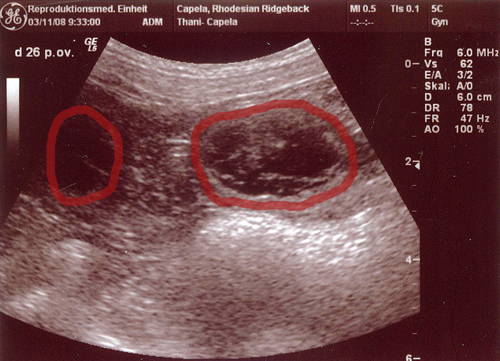

| Es ist heute so weit gewesen. Der große Tag den wir voll Spannung erwartet haben stand vor der Tür: Thani´s Ultraschalltermin in der Reproduktionsmedizinischen Einheit der Ti Ho Hannover. Das professionelle Ärzteteam wird mit Sicherheit ihren Teil dazu beigetragen haben das wir stolz berichten können das Thani tragend ist. Es haben sich zahlreiche Fruchthüllen gezeigt, die schön gleichmäßig in Größe und Abstand aneinander gereiht waren. Wie auch bei ihrer ersten Ultraschalluntersuchung beim A-Wurf war sie auch diesmal recht lebhaft und konnte die Untersuchung nicht ruhig ausharren. Sie stand allerdings auch mit dem Hinterteil zum Ultraschallgerät und versuchte die ganze Zeit neugierig zu gucken was sich da hinter ihrem Rücken abspielte. Auch das ständige Wedeln mit der Rute oder dem Team ein Nasenstüber zu verpassen, brachte etwas Unruhe ins Bild. Dennoch hat es gereicht um von manchen auch die kleinen Herzchen schlagen zu sehen. Ajani und Thani haben ganze arbeit geleistet, sehr schnell und ebenso sehr effektiv. Nun sind wir ganz gespannt was sich uns in ein paar Wochen offenbaren wird….. Eins können wir versprechen, es wird uns eine ereignisreiche Adventszeit bevorstehen. Die Instinktsicherheit dieser beiden RR´s hat uns wieder mal gezeigt das man den Dingen ihren lauf lassen , und man sich nicht zu viele Gedanken machen sollte. Ob nun der Deckakt schnell wie normal üblich über die Bühne geht oder man die Hündin nicht sofort zur Ruhe bettet, hat uns auch dieses mal gezeigt das es mit Sicherheit nicht ausschlaggebend ist. Karolina kann bestätigen das es richtig lustig war Thani danach zu sehen :-) wie ausgelassen und fröhlich sie herumgehopst ist und sich genüsslich vor Ajani auf dem Boden gewälzt hat. Der Bräutigam fand es dann zwar doch etwas merkwürdig als sie gleich angefangen hat Löcher im Garten zu buddeln, aber ich hätte ihr nie diese harmonischen Erlebnisse rauben wollen indem ich sie gleich auf ihren Hundeplatz geschickt hätte. Aber wer Thani kennt weiß das das nicht zu ihr passen würde :-) Nun können wir etwas gelockerter dem großen Tag entgegenschauen und werden unser möglichstes tun Thani optimal zu unterstützen. Unsere Große ist sehr entspannt und befindet sich in bester Kondition. Wie es sich für eine Trächtigkeit gehört glänzt ihr Fell mehr als zuvor und ein kleines Bäuchlein lässt sich bei scharfem Blick auch schon erkennen. Der Appetit ist zwar etwas gezügelt aber das ist ja auch eine weitere Begleiterscheinung zu diesem Zeitpunkt. Wir